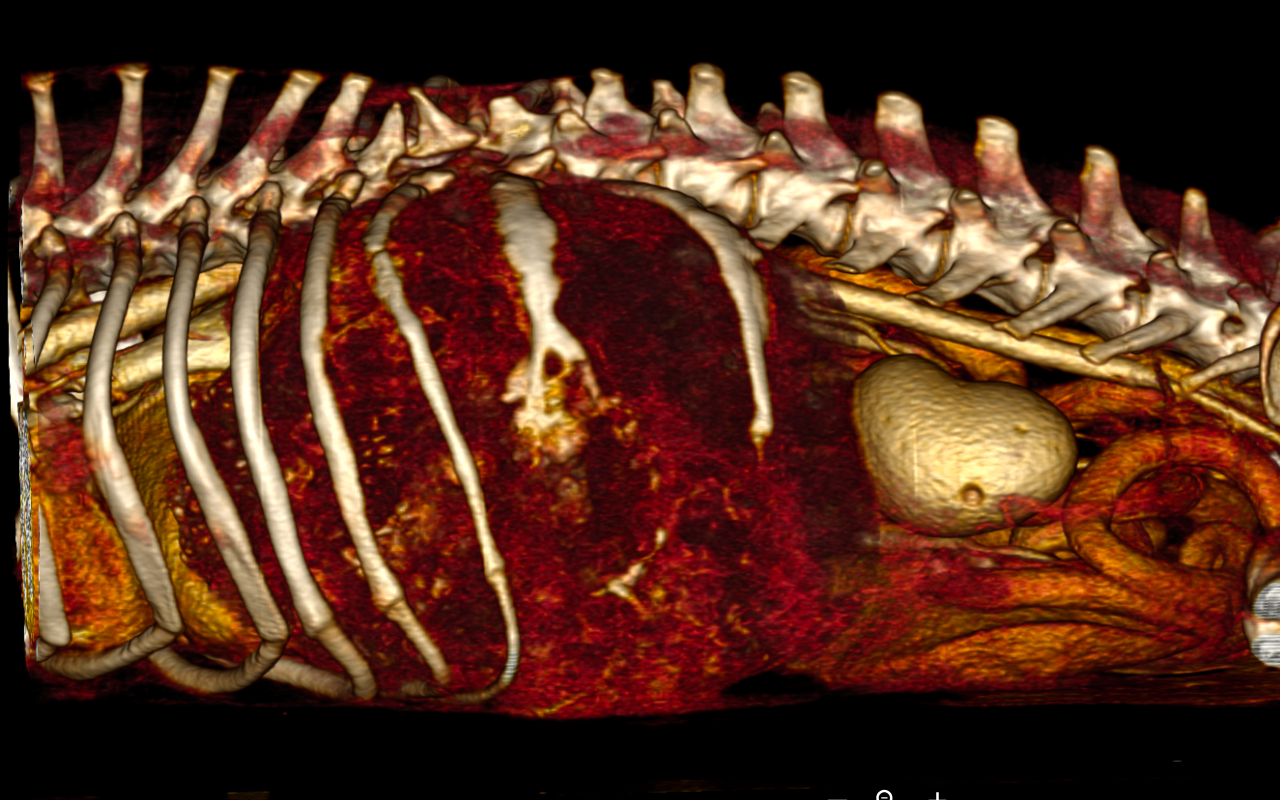

具体的には腫瘍の形状・大きさ、転移の有無、結石の有無、異物の有無など様々な病態に使用され、現在の獣医療に欠かせない診断ツールの一つになっております。また手術経過を立てる際に3D画像も撮影することができ、より安全に手術を行うことが可能となります。

下記の画像は当院で撮影した肋骨腫瘍の症例のCT画像です。超音波検査では腫瘤が巨大すぎて発生源の特定が困難でしたが、CT検査を実施し肋骨の発生源の特定、大きさ、他の臓器の浸潤度合いなど判断することができました。

この子は肋骨3本ごと切除する手術にも耐えてくれて手術も無事成功し今は元気に過ごしております。